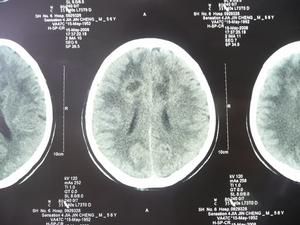

額葉腫瘤CT圖3.錐體束損害症狀額葉腫瘤時病灶對側腹壁和提睪反射的減弱消失以及同時出現強直性跖屈反射,常為早期症狀,隨著腫瘤的繼續增大及對運動區的侵犯程度病灶對側可出現肌張力增高,腱反射亢進,同時往往伴有踝陣攣、臏陣攣和腕陣攣等,最後可出現病灶對側的不同程度的癱瘓,Babinski征是皮質脊髓束病變的一種有代表性的重要體徵,額葉皮質運動區任何部位的腫瘤都可以出現。

額葉腫瘤CT圖主要特點如下:

(1)額葉底部腫瘤、(2)額極腫瘤、(3)額葉矢狀竇旁腫瘤、(4)額葉下部腫瘤。